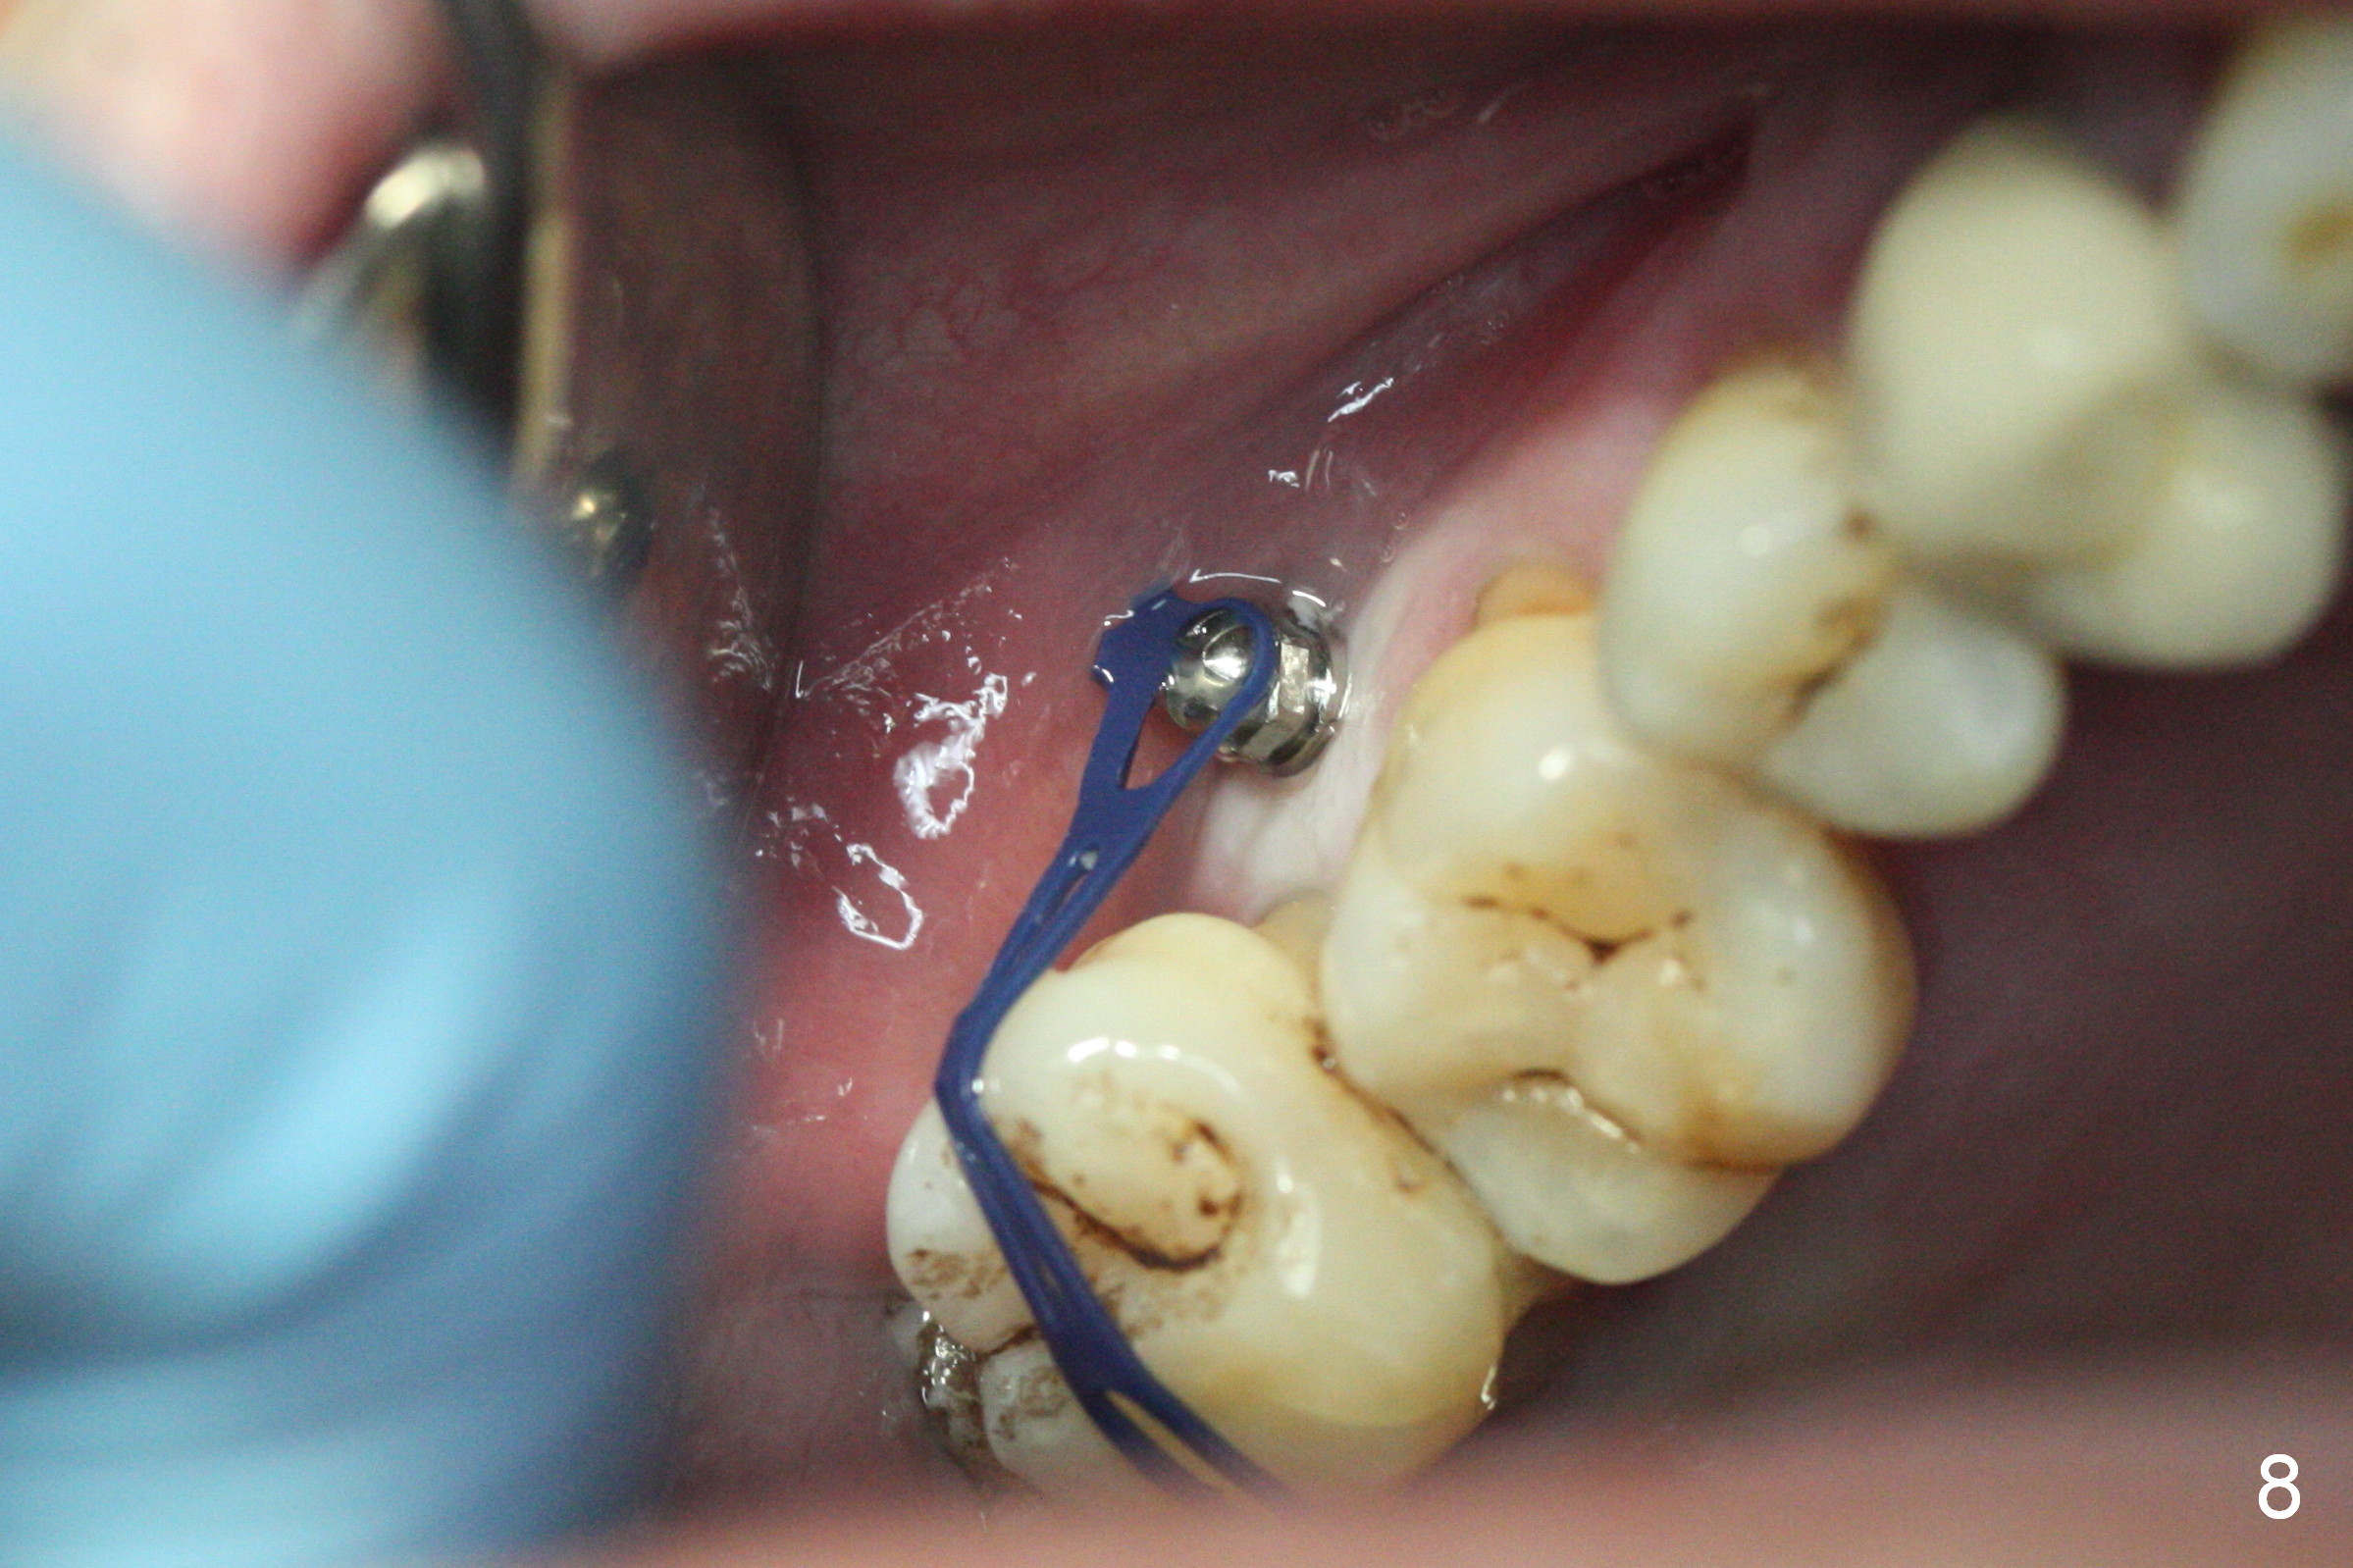

Two days post #31 implant placement, the patient returns for orthodontic intrusion of the tooth #2 with mini-implants (Fig.1). The palatal cusps have been trimmed (Fig.2 ^), since they almost contact a healing abutment at #31(*, Fig.3). Two mini-implants are to be placed mesiobuccal and distopalatal to the affected tooth. After minimal injection of Lidocaine, a 1.6x6 mm Tomas implant is placed in full length mesially (Fig.4), while the other (1.6x8 mm) half way (Fig.4). Following change in implant site mesially (Fig.6 >), the implant is half inserted (Fig.5). It appears that the tip of the distal implant is toward the tooth #1 (Fig.5). After withdrawing the implant partially, it is re-directed to apparently ideal trajectory (Fig.7). Ideally the mesial implant (Fig.8) should have been placed partially initially (Fig.4,5,7) so that the trajectory could have been able to be changed.

The buccal implant becomes loose in 2-3 months. When the wound heals (Fig.9 <), a 1.6x`10 mm implant is placed with the help of PAs for trajectory (Fig.10,11) and in the nonkeratinized gingiva (higher, the crestal bone may have been traumatized by previous implant placement, Fig.12). Two months later, the tooth #2 is partially intruded (Fig.13). A provisional (Fig.14 P) is fabricated in the osteointegrated implant at #31 with supraocclusion so that the remaining dentition has no occlusal contact (*). The periodontally compromised tooth #2 becomes in buccoversion in 2 months. The provisional is removed, while a lingual button is placed in the buccal surface of the tooth #2 (Fig.15). With power chain attached to the lingual mini-implant, the tooth #2 is lingualized in 2 months. The provisional and the implants are reused for final intrusion (Fig.16). The treatment is nearly 11 months. The buccal implant, although placed in the movable mucosa, remains stable and healthy (Fig.17). The tooth #1, as a guiding plane (to prevent #2 from distalization during intrusion), is not extracted after intrusion is completed.